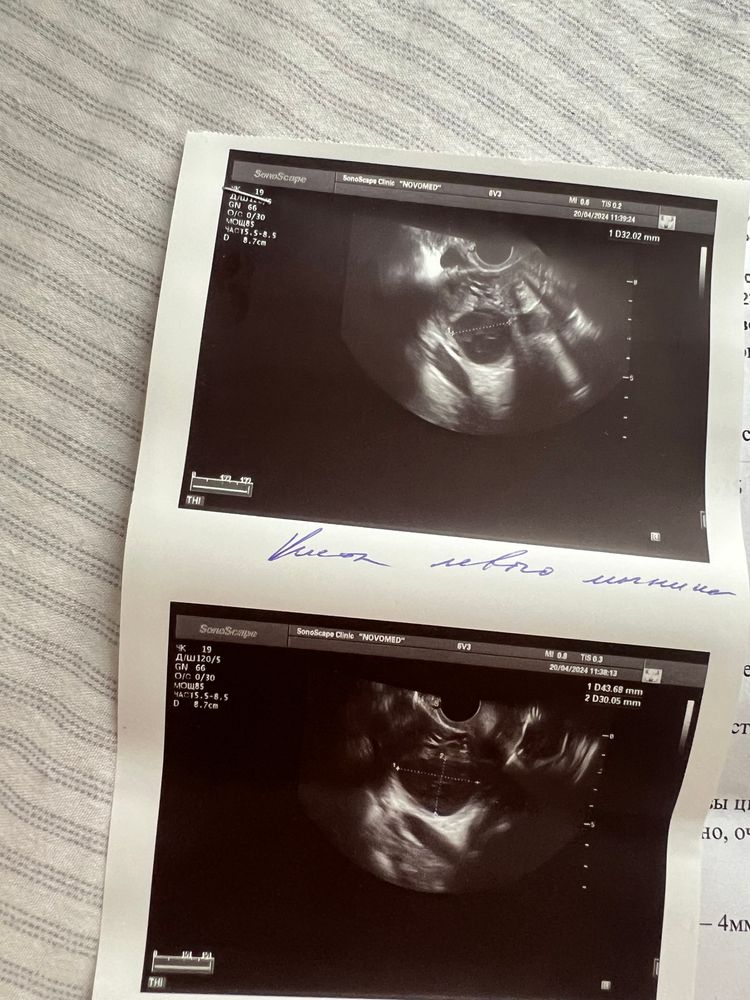

из-за кисты месячные могут прийти с задержкой большой. Беременность исключена

Анна, почему исключена? У меня была задержка 5 дней , пошла на узи там была киста желтого тела , сказали нет беременности, но через пару дней беременность подтвердилась

У меня было, но ничего страшного...ушла за 2 цикла размером 5 см..Задержка может быть, но может и не быть... К стати и беременность тоже нельзя исключать, если это киста ЖТ.. Вот если б фоликулярная, тогда да...